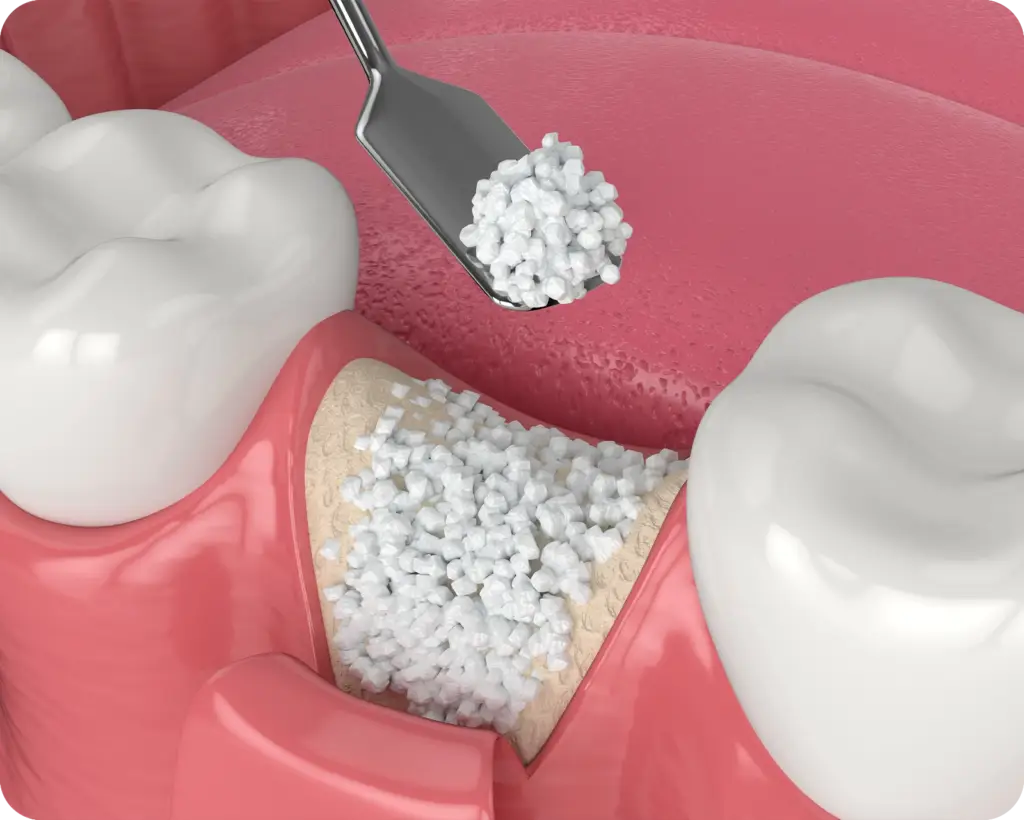

Injertos óseos: En algunos casos, puede ser necesario realizar injertos óseos para mejorar la calidad y cantidad del hueso en el área donde se colocarán los implantes dentales. Los injertos óseos pueden obtenerse de diferentes fuentes, como el propio paciente (autólogo), bancos de tejidos o materiales sintéticos. Estos injertos proporcionan una base sólida y suficiente para la colocación de los implantes.

Preservación alveolar: es la técnica que se utiliza para evitar la reabsorción ósea luego de una extracción dental, evitando el colapso del hueso. Se logra mediante la utilización de biomateriales. Esta se realiza posterior a la extracción dental y puede ser realizada previo a la colocación de implantes.